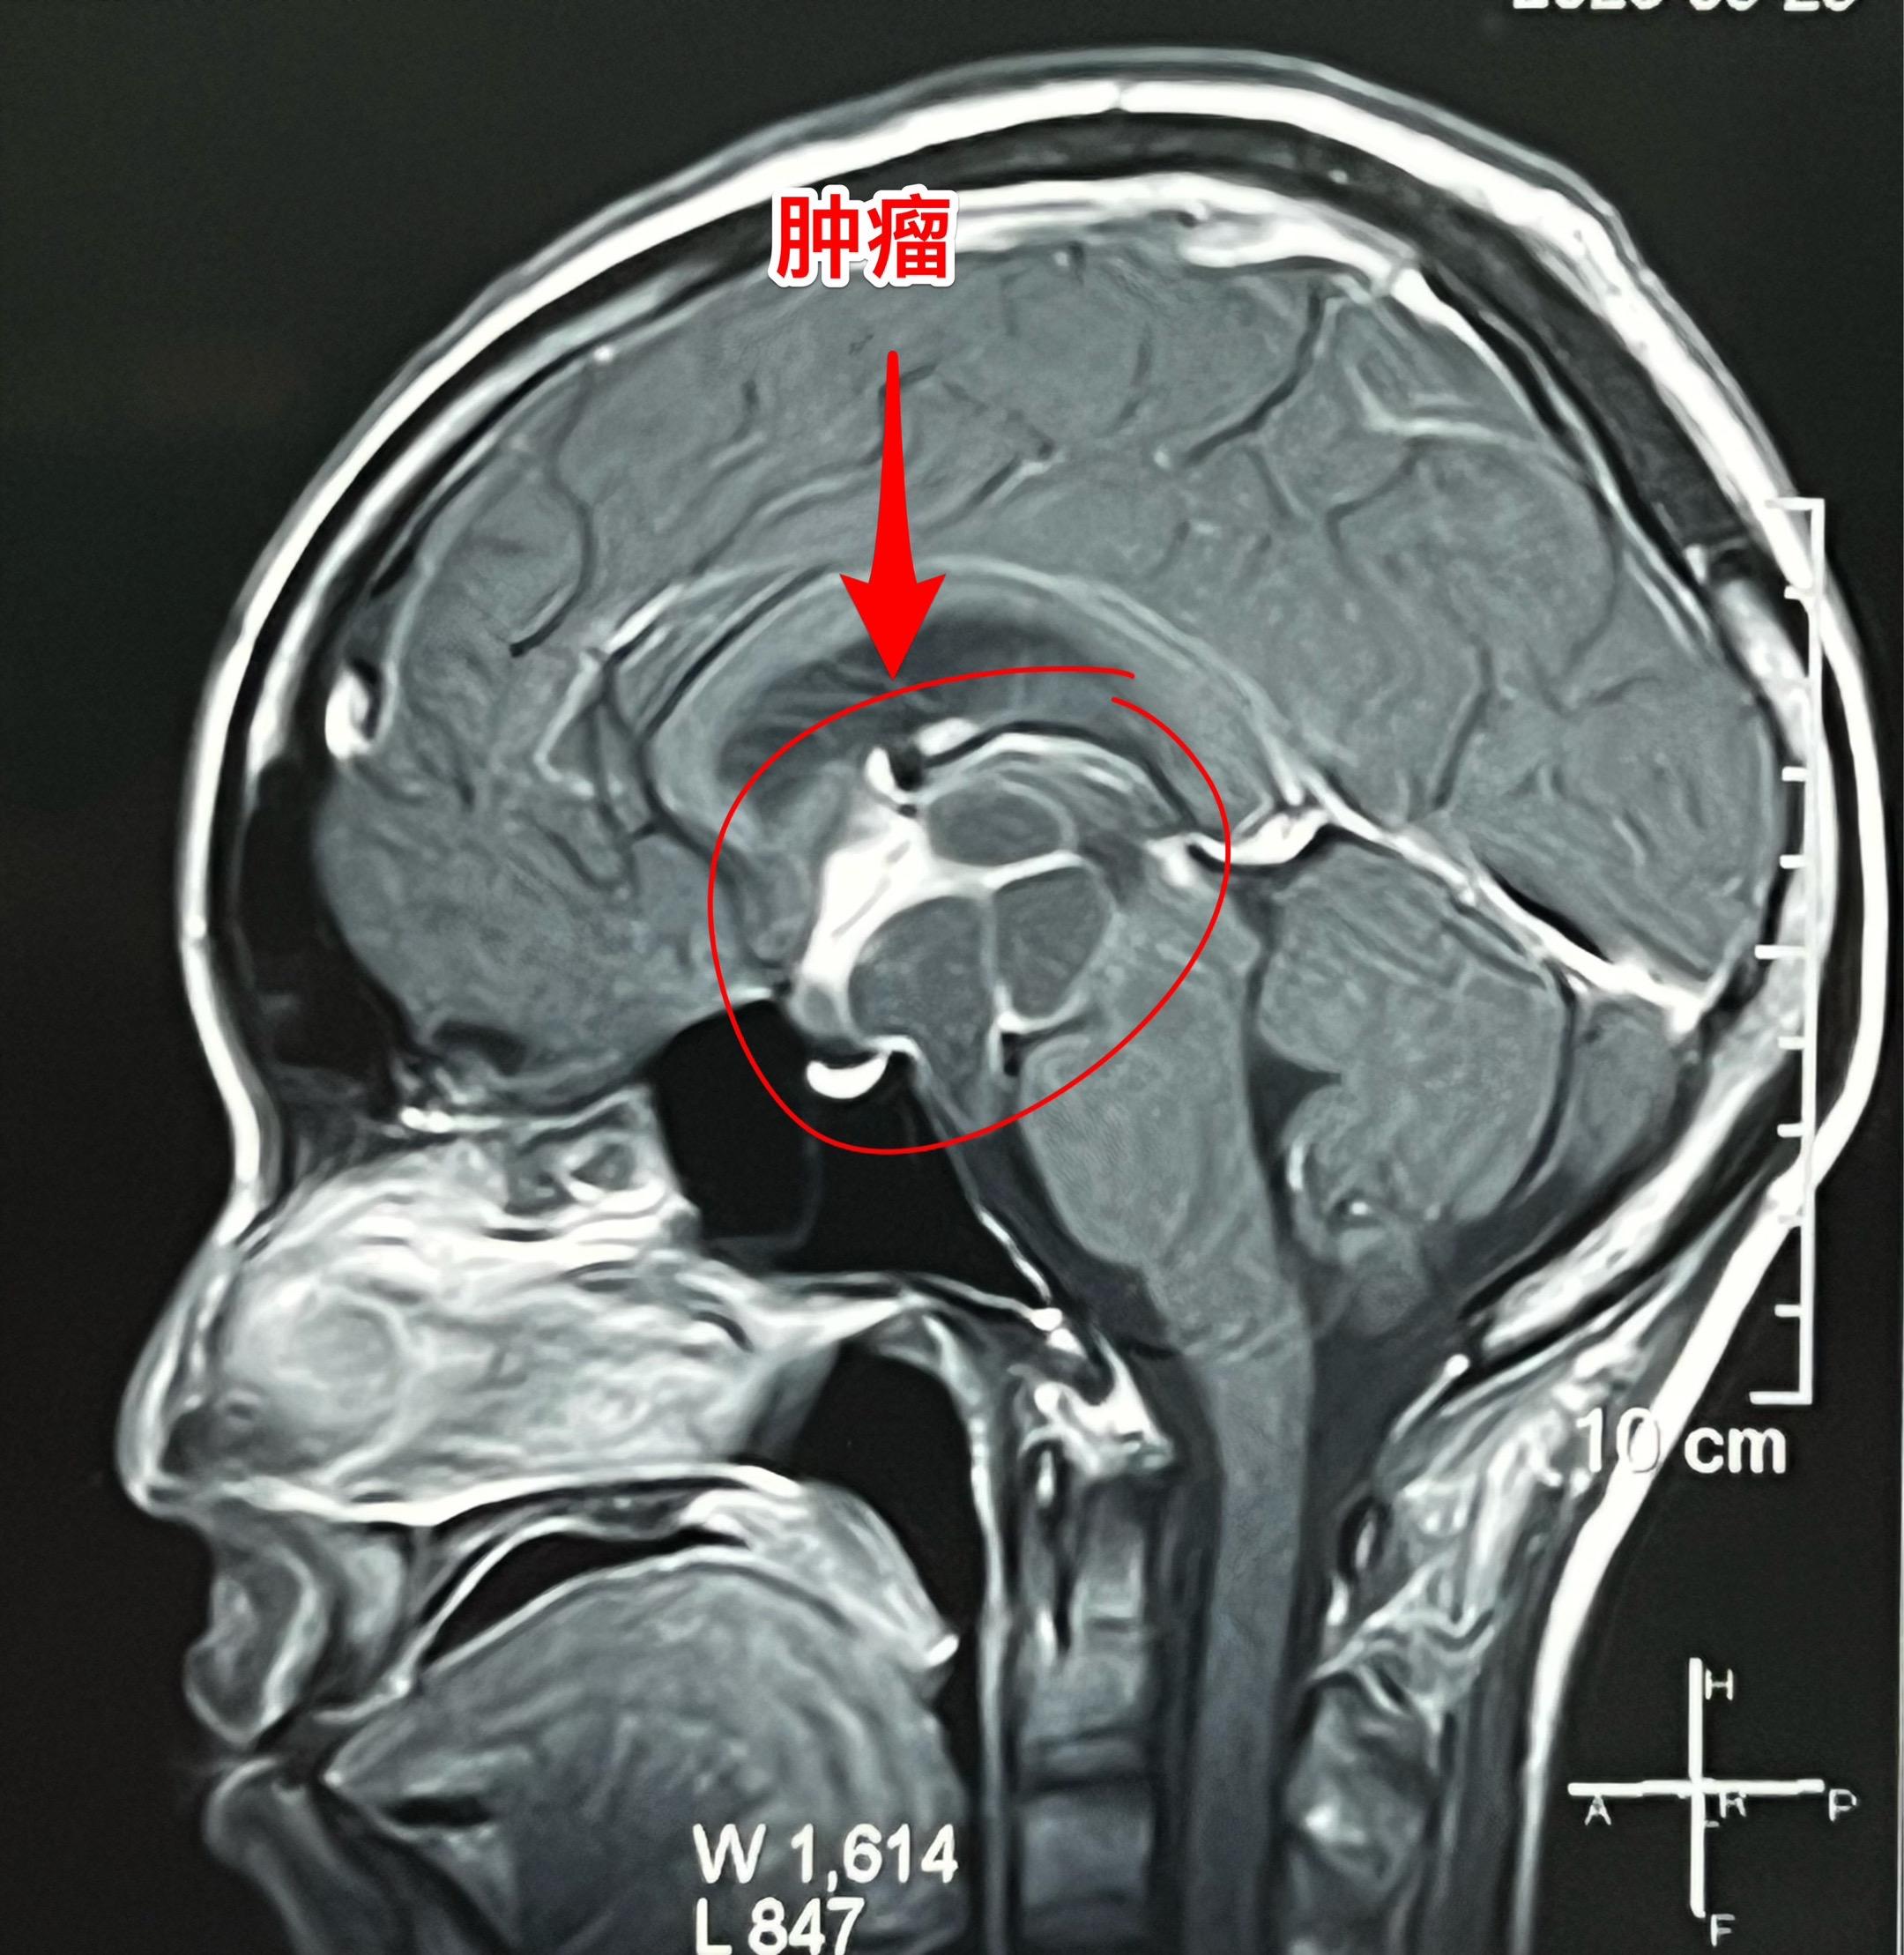

20岁女大学生生病三年身体虚弱如林黛玉。洛阳市女学生,三年前开始出现食欲下降,伴体重减轻。一年前出现多饮多尿症状、内分泌紊乱。怀疑是糖尿病,未得到有效治疗,症状越来越严重。2025.9病人出现头痛、呕吐、嗜睡。在洛阳市某医院就诊,行磁共振检查发现鞍区肿瘤伴有脑积水。于9月23日行脑室引流术,手术后病人头痛、呕吐症状好转。 9月28日到我院住院。住院时病人精神状态很差,体重才80斤,消瘦、面色苍白,看起来如林黛玉一样弱不禁风。(发病前体重一百多斤。) 9月30日作了开颅手术,切